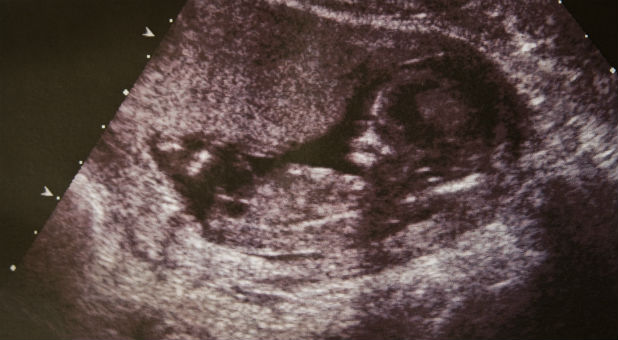

With nearly one million abortions annually in the U.S., abortionists are killing close to 13,000 children every year who are often fully developed and can survive outside the womb. The Centers for Disease Control reported in 2012 that 1.3 percent of abortions were committed at 21 weeks’ gestation and later.

The New England Journal of Medicine reports that with medical intervention, the survival rate of babies born at 26 weeks is as high as 81 percent—with 75 percent of those children having no severe impairments.